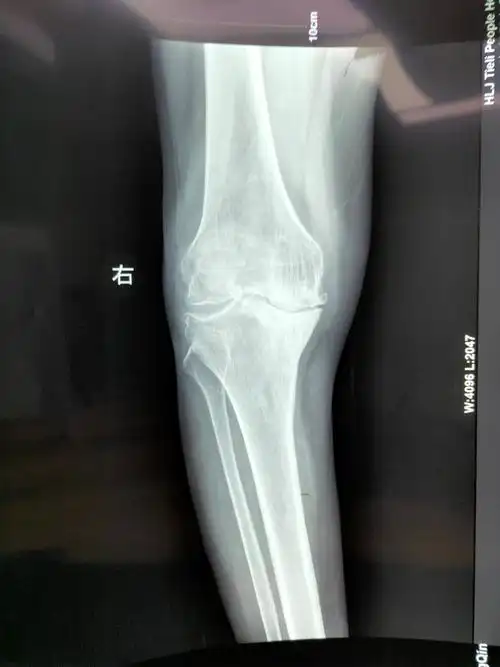

术前检查的膝关节x线

术前膝关节正位x线片

膝关节 x 射线,膝部x光片

大夫您好,我现在手术完23天,基本上没怎么掰腿就到了120度-袁锋副主任